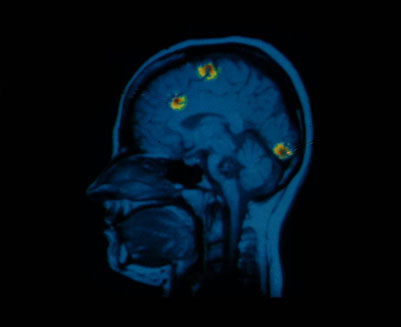

Un elemento central en el diagnóstico de estos padecimientos es la tomografía PET, o "tomografía por emisión de positrones", que fue desarrollada en Suecia por un grupo de médicos entre los que se encuentra un uruguayo: Henry Engler, que forma parte del Centro PET de la Universidad de Uppsala.

En una entrevista realizada en 2004 por la radio El Espectador, este médico explicó que con la tomografía PET se puede ver la funcionalidad de los órganos, por ejemplo del cerebro, y determinar sus reacciones a distintos estímulos. "El pánico a los espacios abiertos, el pánico por las arañas y las víboras, eso tiene una representación dentro del cerebro que hemos podido ubicar en nuestro centro", señaló Engler en aquel entonces.

Pero Uruguay está lejos de contar con una tecnología de ese tipo. "Los médicos acá se basan en su ojo clínico, combinado con lo que nosotros le podemos transmitir", señala Picky, con la decepción de quien entiende cuánto más fácil sería el diagnóstico si se contara con estos avances.